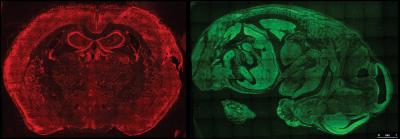

BOSTON -- In biology, as in real estate, location matters. Working copies of active genes -- called messenger RNAs or mRNAs -- are positioned strategically throughout living tissues, and their location often helps regulate how cells and tissues grow and develop. But to analyze many mRNAs simultaneously, scientists have had to grind cells to a pulp, which left them no good way to pinpoint where those mRNAs sat within the cell.

Now a team at the Wyss Institute of Biologically Inspired Engineering at Harvard University and Harvard Medical School, in collaboration with the Allen Institute for Brain Science, has developed a new method that allows scientists to pinpoint thousands of mRNAs and other types of RNAs at once in intact cells -- all while determining the sequence of letters, or bases, that identify them and reveal what they do.

The method, called fluorescent in situ RNA sequencing (FISSEQ), could lead to earlier cancer diagnosis by revealing molecular changes that drive cancer in seemingly healthy tissue. It could track cancer mutations and how they respond to modern targeted therapies, and uncover targets for safer and more effective ones.

The method could also help biologists understand how tissues change subtly during embryonic development -- and even help map the maze of neurons that wire the human brain. The researchers reported the method in today's online edition of Science .

By analogy, the scientists sought to fix RNA in place in the cell, make a tiny ball with many matching DNA replicas of each RNA, then adapt next-gen DNA sequencing so it worked in fixed cells. The four flashing colors would reveal the base sequence of each replica DNA, which would tell them the base sequence of the matching RNA from which it was derived. And those sequences would in theory provide an unlimited number of unique addresses – one for each of the original RNAs.

They succeeded by selectively turning on just a fraction of those flashing dots at any given time, so they could distinguish single balls of replica DNA flashing across the cellular landscape.

Then Daugharthy hacked a commercial DNA sequencing kit, which enabled the team to sequence 30 bases, more than enough to provide each replica DNA with a unique address. In this way the team could create a composite image representing the sequence, and location, of RNA corresponding to every gene in the human genome.